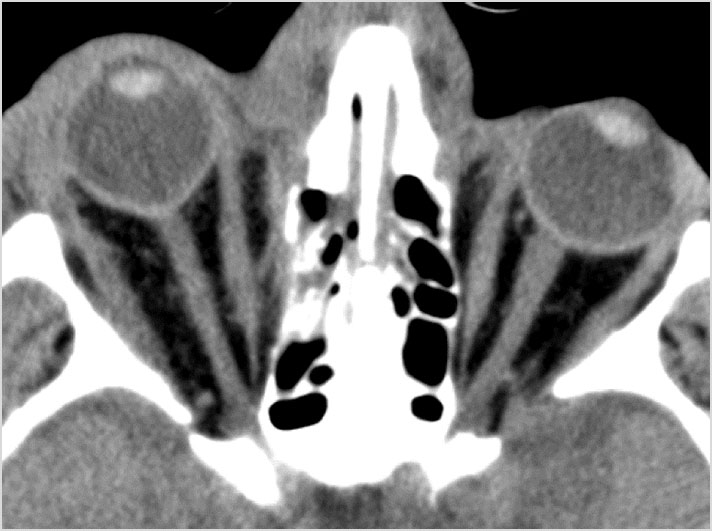

Fronto-Naso-Ethmoidal Complex

The mesial naso-orbito-ethmoid complex is fractured. Specifically, there is bony injury of the nasal bones or the frontal process of the maxilla and the medial walls of the orbit are abnormal.

There is injury of the ethmoid complex. Specifically, the ethmoid roof, olfactory fossa and the cribriform plate are fractured and/or significantly dehiscent.